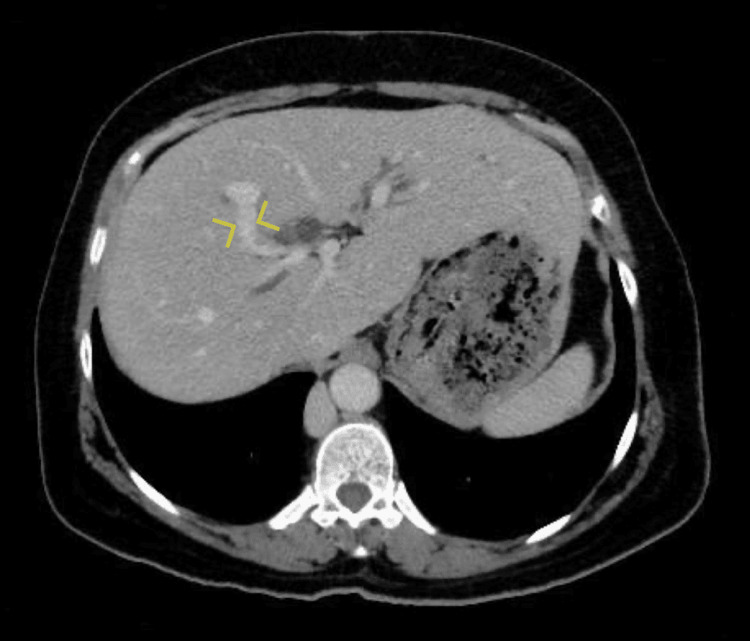

This anterior branch continues towards the porta hepatis as a portal vein, and the posterior branch joined by the splenic vein continues laterally to the right and enters the liver at its edge close to segment VI as the second portal vein (Figure 2). The two portal veins were noted to communicate inside the liver parenchyma near segment VIII (Figure 3).